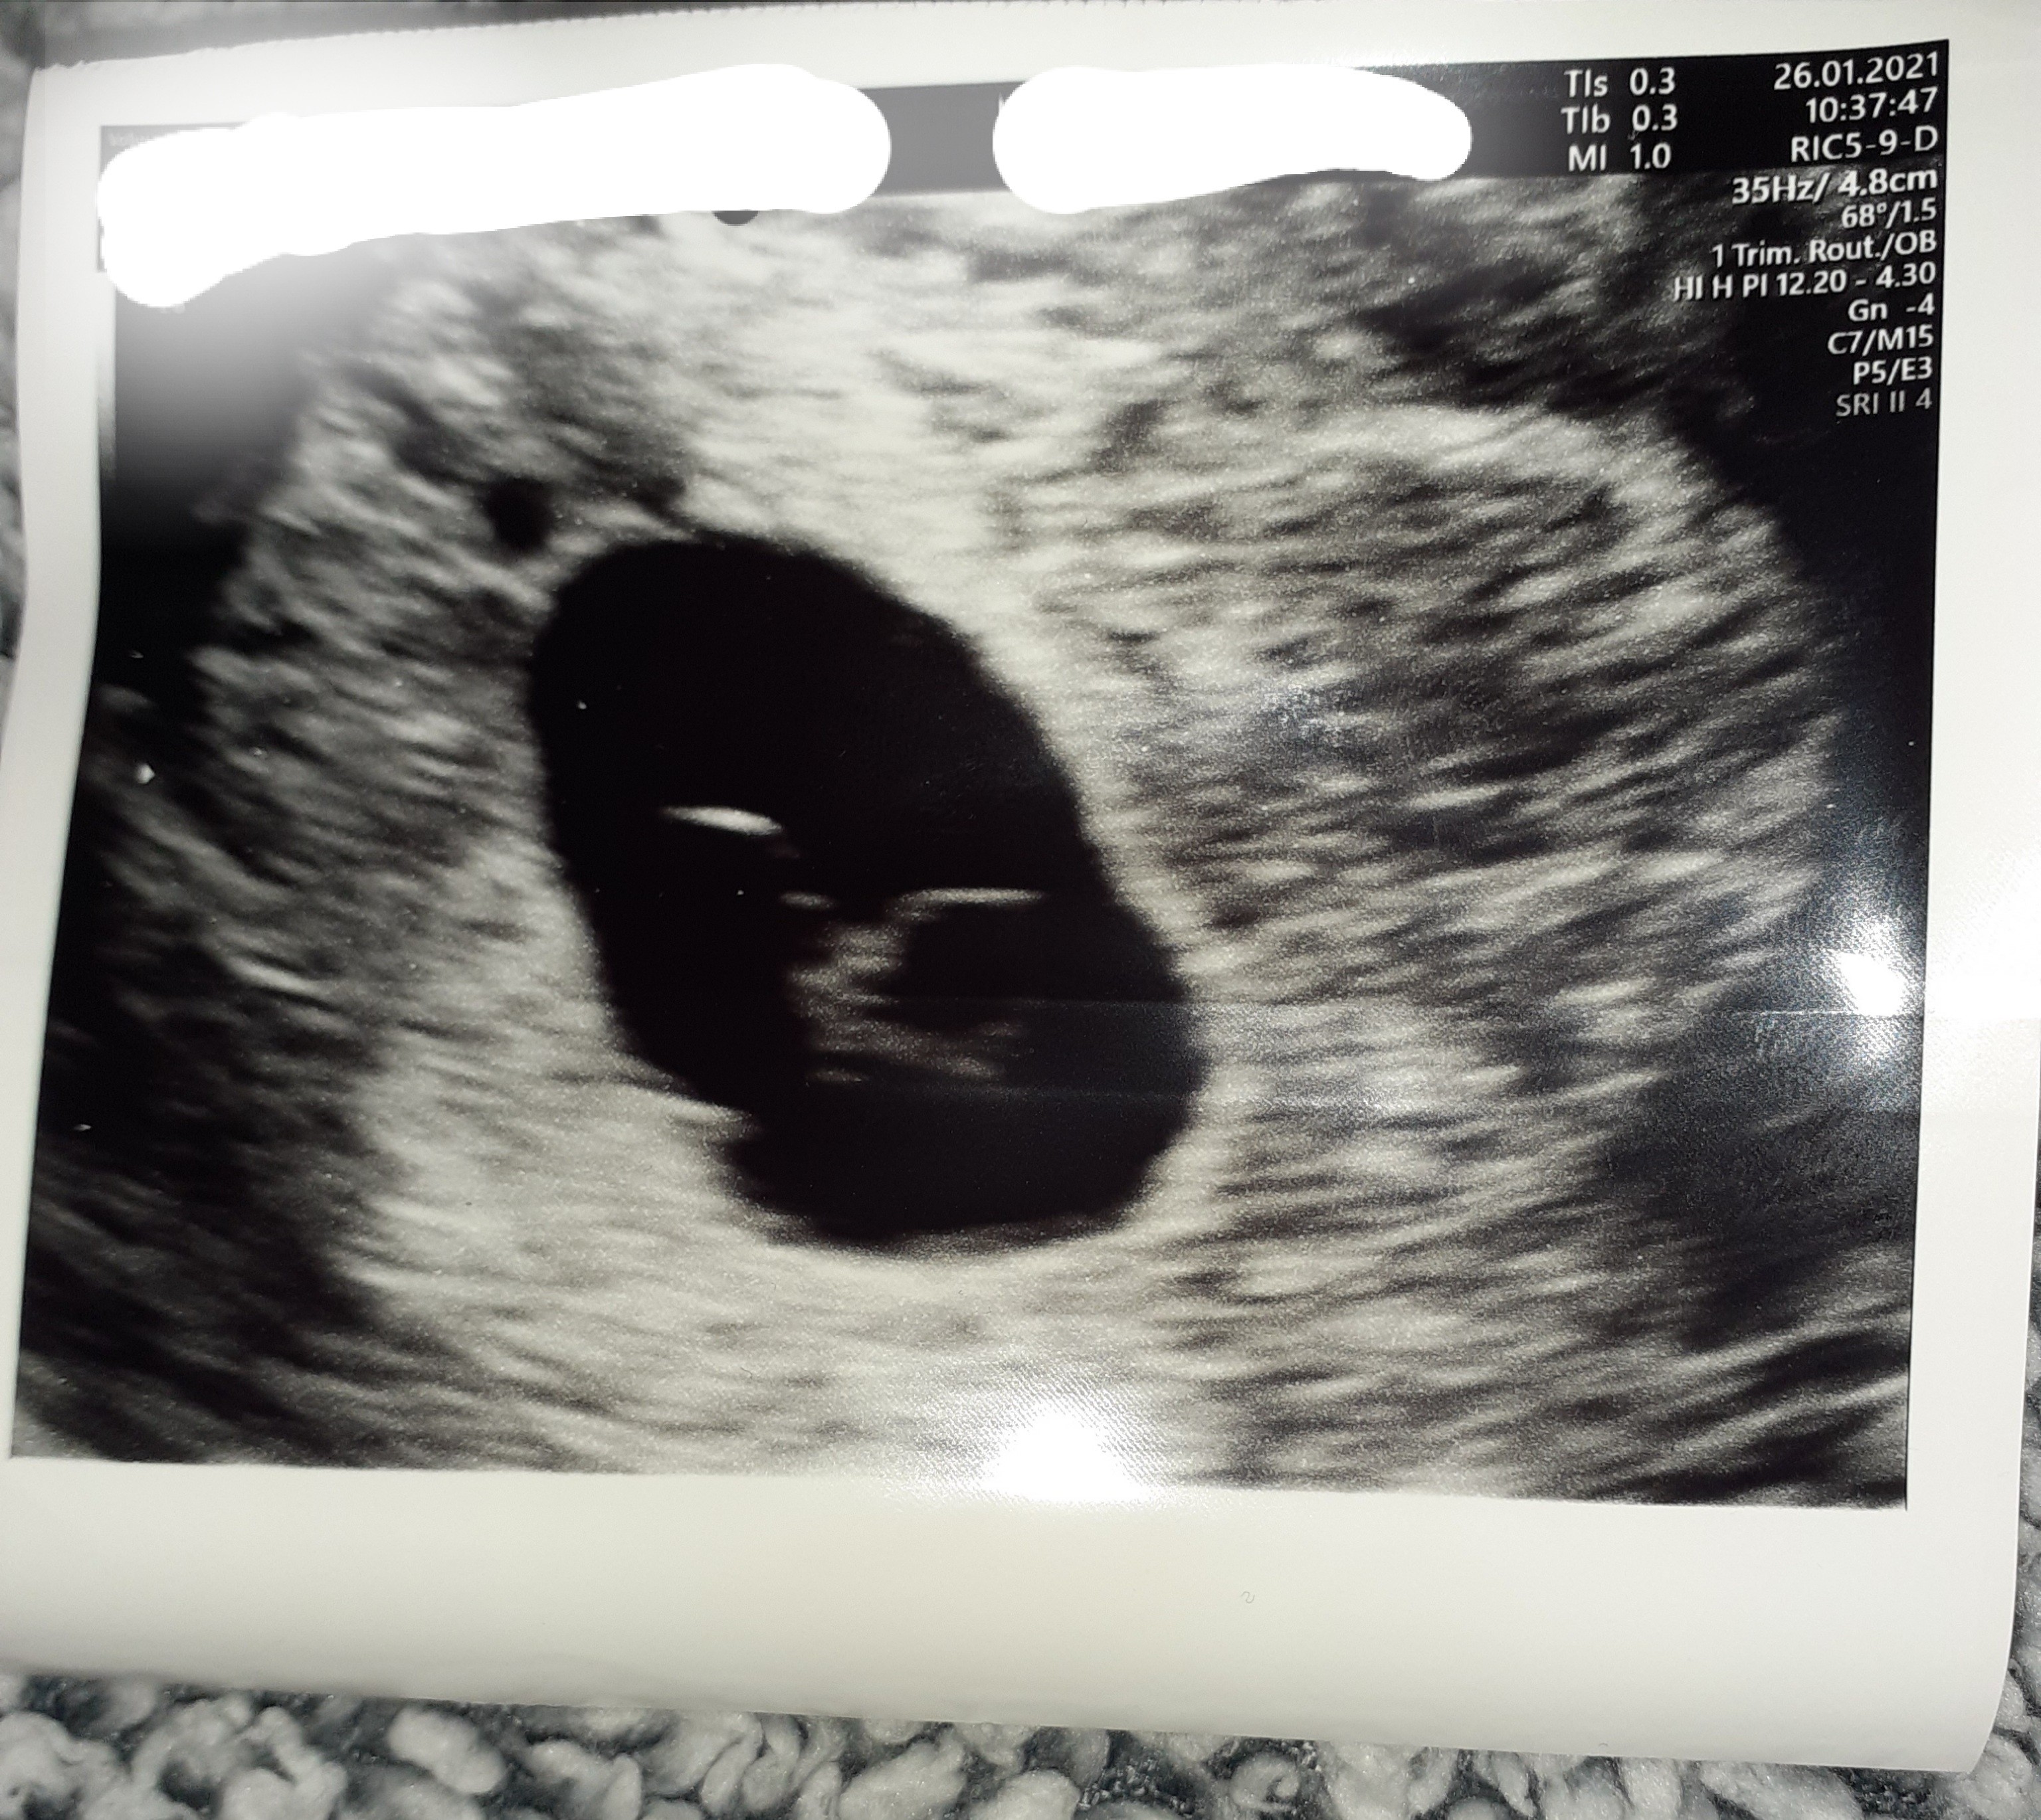

Położna zrobiła usg, stwierdziła że nie ma akcji serca, że płód według niej obumarł około 6 tygodnie bo jest zbyt mały na 8tc.

Zarodek ma 4.2mm i według położnej jest martwy bo nie ma akcji serca.

Niestety sytuacja wygląda nieciekawie i z tego co widzę na zdjęciu oraz z tego co piszesz - brak zauważalnej akcji serca w 8 tygodniu ciąży (a uwierz mi ze jeśli widać zarodek to nie da się przegapić akcji serca, ponieważ ono jest na tym etapie dużą częścią zarodka) to szanse na to, że Twoje maleństwo jeszcze walczy są praktycznie minimalne.

W obecnej ciąży zatrzymał się jeden z moich bliźniaków i przez wiele tygodni wyglądał właśnie tak jak Twoje maleństwo na zdjęciu 😥